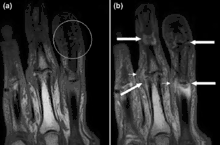

Magnetic resonance images of the fingers in psoriatic arthritis. Shown are T1 weighted axial (a) pre-contrast and (b) post-contrast images exhibiting التهاب الأصبع due to مصطلحات تشريحية التهاب زليل الوتر at the second finger with enhancement and thickening of the tendon sheath (large arrow). Synovitis is seen in the fourth proximal interphalangeal joint (small arrow).